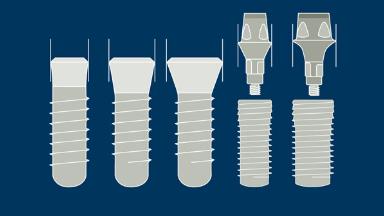

A geometria do corpo dos implantes geralmente pode ser dividida em três partes: a parte endóssea, que se encontra dentro do osso, a seção transmucosa, que fica nos tecidos moles entre o osso e a cavidade oral, e a interface com os componentes protéticos. Em cada uma dessas três partes, existem outras características da geometria e variações na sua forma, atributos e dimensões. Existem também variações no material do corpo do implante e no tratamento de superfície. Essas variações serão descritas e discutidas nos seguintes Objetivos de Aprendizagem.

- descrever as variações na interface protética do implante

- descrever as variações da seção transmucosa do implante

- descrever as variações na parte endóssea do implante